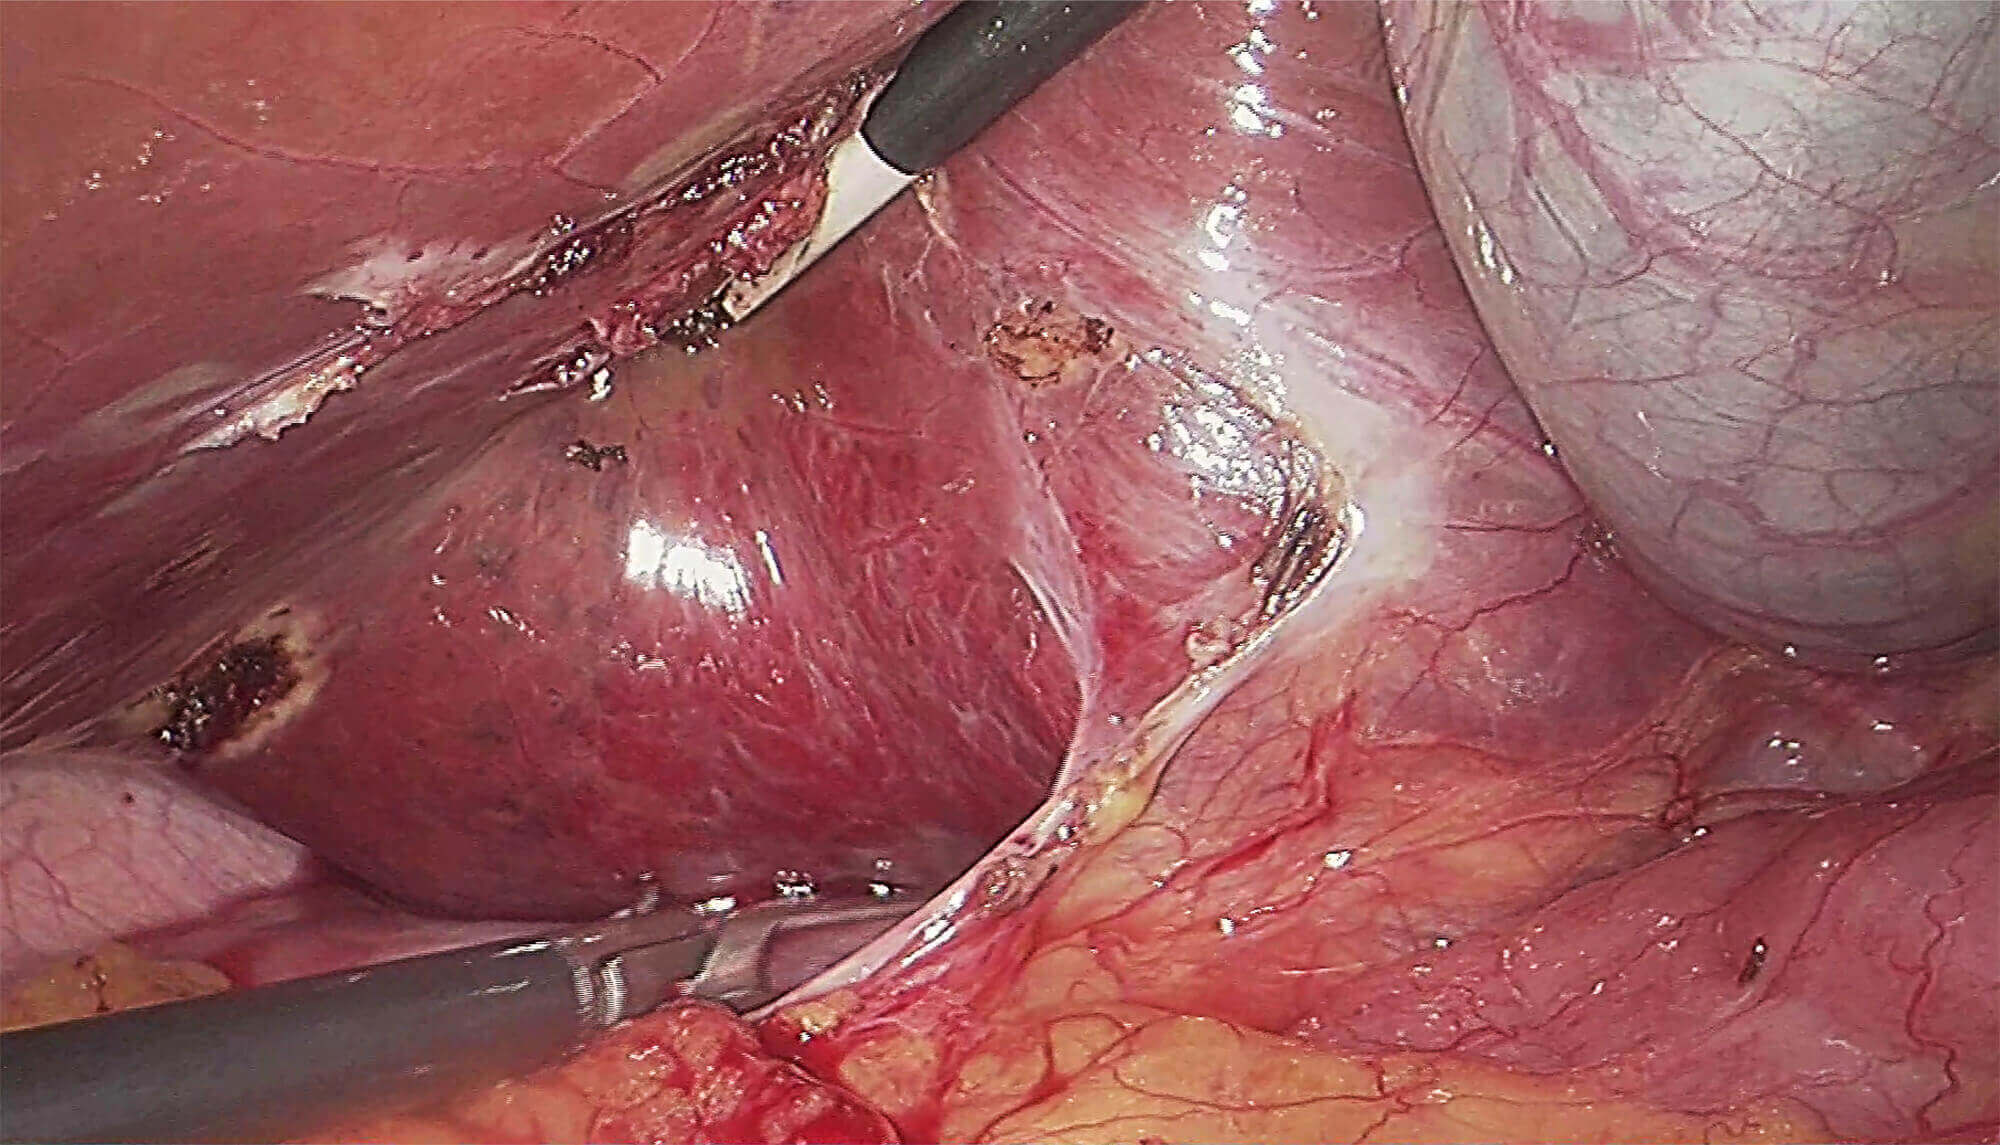

• 腹腔镜

高清晰度

采用蓝宝石镜面设计

高密封设计,提高耐用性

可高温高压或低温等离子灭菌

直径5mm/10mm、视角0°/30°可选

超腹联合 双镜联合

领航微创外科精准诊疗新标准